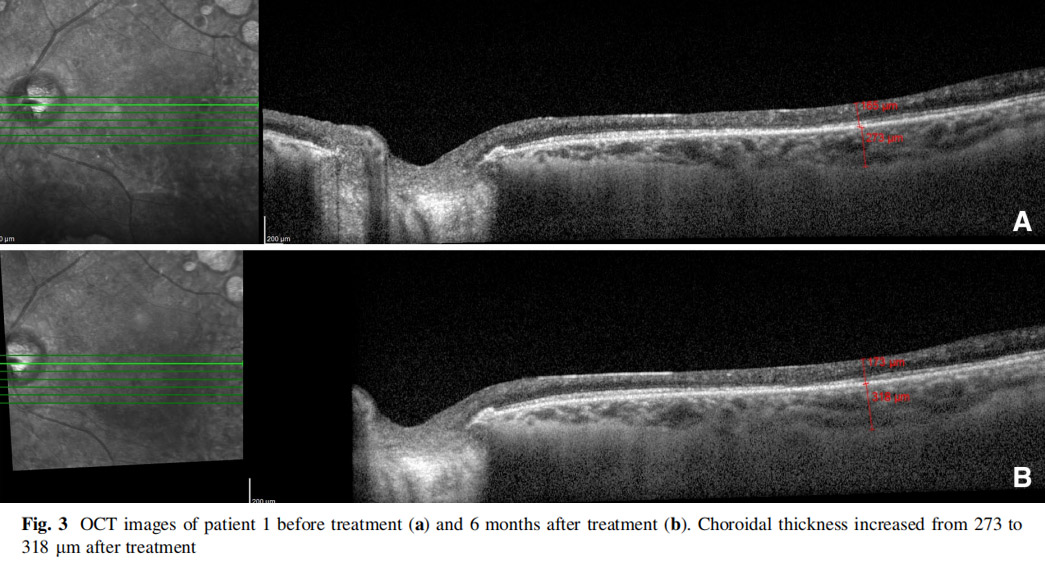

患者左眼接受AD-MSCs治療,6個(gè)月后視力提高至2米處數手指(CF)水平,視野中央島狀結構擴大,如圖1所示,左眼mfERG顯示改善(圖2),脈絡(luò )膜厚度從273μm增加至318μm(圖3),黃斑厚度和RNFL沒(méi)有變化。